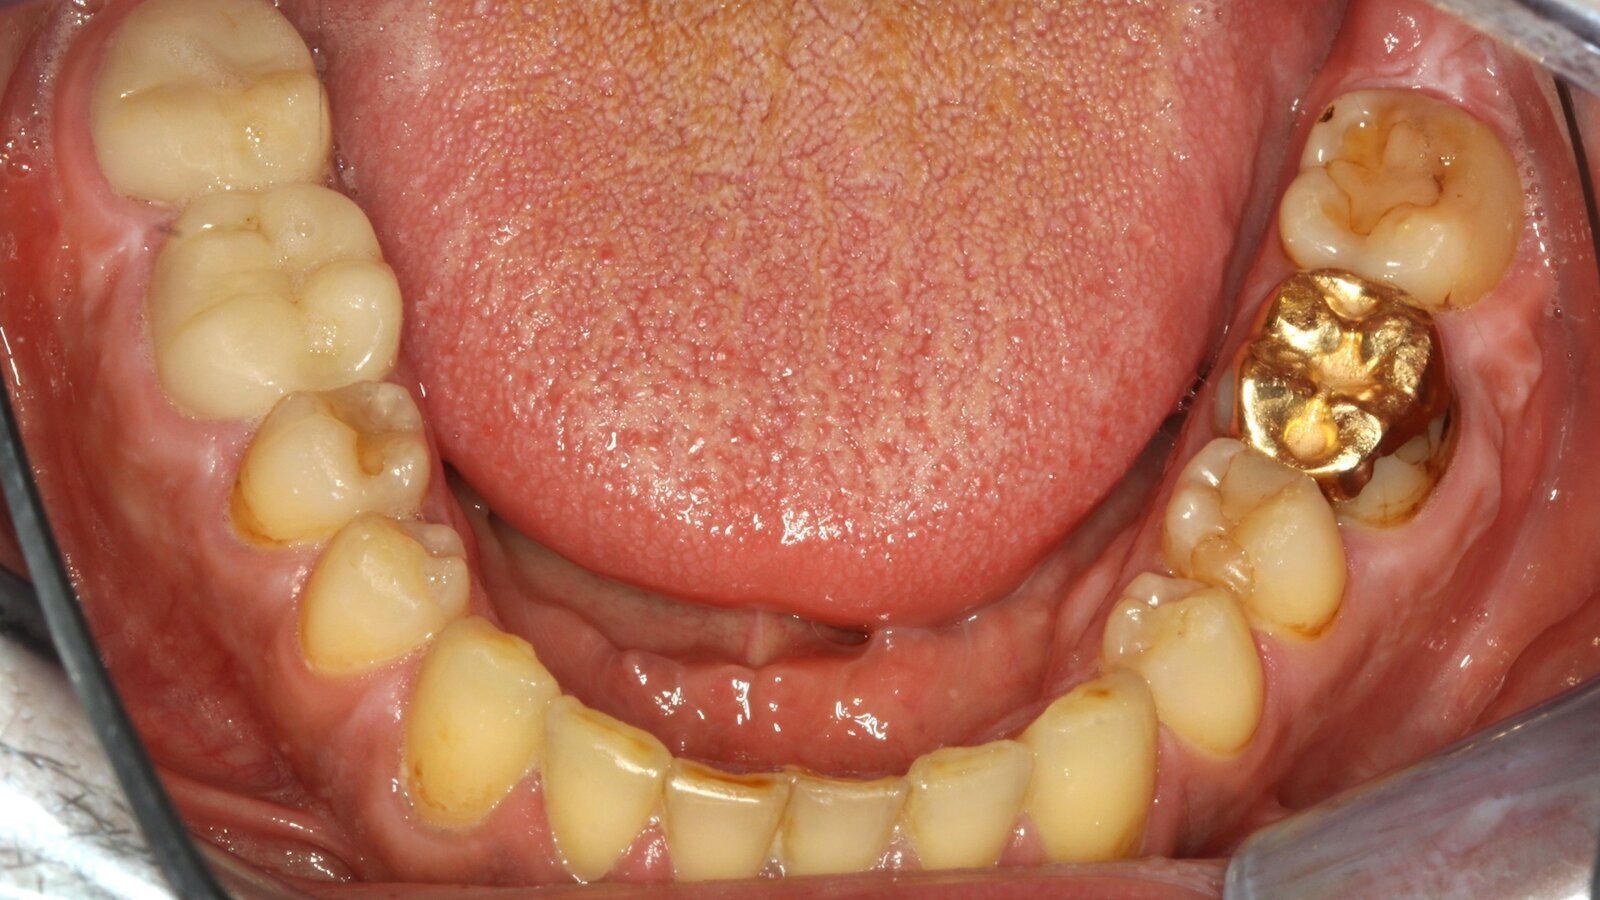

Paciente con endocarditis y lesiones de caries activas en el que se siguió para su tratamiento el Concepto de Prevención Personalizada.

Paciente tiene 39 años con valvuloplastia, insuficiencia valvular y endocarditis, que toma regularmente 100mg de ácido acetilsalicílico como anticoagulante. En lo que se refiere al estilo de vida, se identifica la alimentación del paciente como promotora de caries, ya que suele consumir alimentos azucarados y seis o siete comidas al día. La salud oral del paciente muestra un riesgo medio de caries con lesiones activas. El riesgo de periodontitis es bajo y presenta gingivitis. Se hacen las siguientes recomendaciones para el tratamiento profiláctico.

• Debido a las lesiones de caries activas y el riesgo de progresión asociado, se recomienda un control posterior más corto a los tres o cuatro meses.